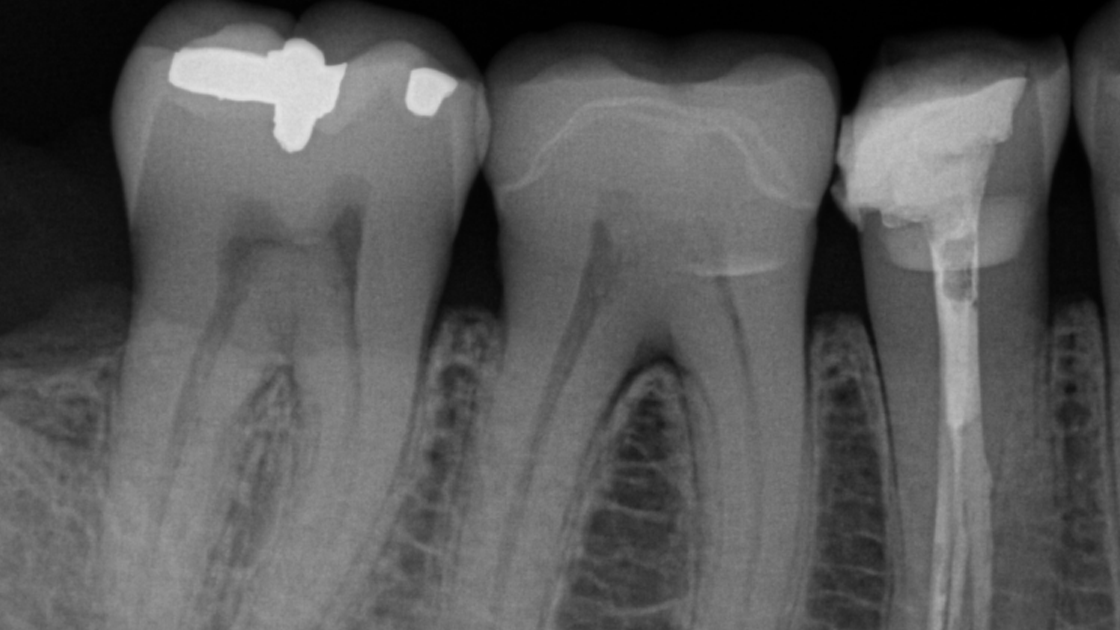

Whether you need intraoral X-rays to assess a symptomatic area or ongoing endodontic treatment, Dentsply Sirona’s intraoral product family has the right solution to support your workflow. The intraoral X-ray portfolio has been engineered to help you reach precision in your X-ray captures, especially when it comes to the positioning of your system. Our intraoral X-ray products are also optimised for easy integration and streamlined workflows, thanks to a state-of-the-art digitalisation and seamless workflow automation. Thanks to their connection to Sidexis 4 and DS Core, the solutions allow you to enter the Dentsply Sirona digital universe and harness all the benefits of this evolving platform.